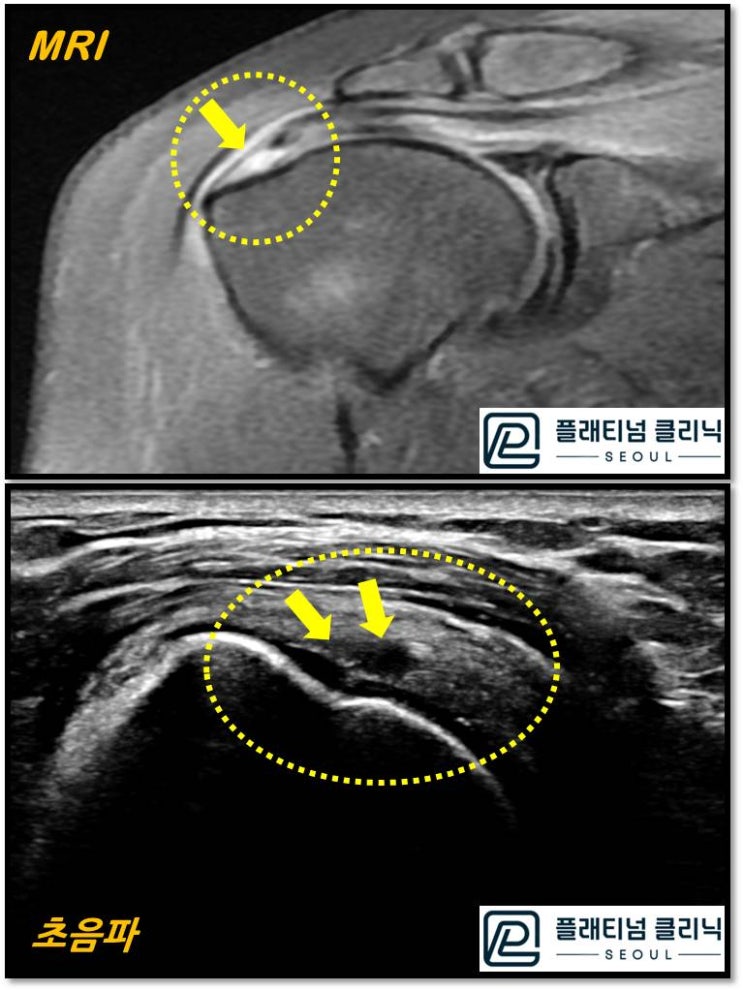

(플래티넘의원) 회전근개 질환 진단시 초음파 만으로도 충분히 진단이 가능합니다.

안녕하세요. 정형외과 전문의 이동규원장입니다. 환자분들이 어깨 질환이 있으면 꼭 MRI 를 찍어야 하냐...

2022. 7. 1.